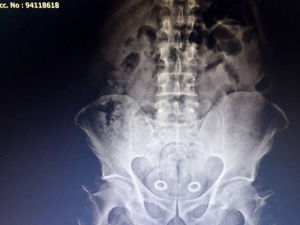

Kars’a Uyuşturucuyu Bağırsaklarında Sokarken Yakalanmıştı